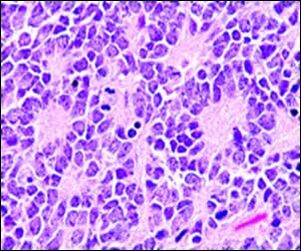

Розетки Флекснера-Винтерштайнера это скопления опухолевых клеток в виде «колеса со спицами» наиболее часто встречающиеся в ретинобластомах и некоторых других опухолях глаза.[2]

В отличие от розеток Гомера Райта центр розетки Флекснера-Винтерштайнера лишен нейропиля с нервными волокнами.[2] Электронная микроскопия показывает, что опухолевые клетки, образующие розетку Флекснера-Винтерштайнера, имеют ультраструктурные особенности примитивных фоторецепторных клеток.[3] Кроме того, просвет розетки имеет те же особенности окрашивания, что и палочки и колбочки[4], из чего можно предположить, что розетки Флекснера-Винтерштайнера представляют собой специфическую форму дифференцировки клеток сетчатки.

Розетки Флекснера-Винтерштейнера не только характерны для ретинобластом, они могут быть обнаружены в пинеалобластомах и медуллоэпителиомах.

Розетки Флекснера-Винтерштейнера были впервые описаны Симоном Флекснером (1863—1946), американским врачом, ученым, администратором и профессором экспериментальной патологии Пенсильванского университета (1899—1903). Флекснер отметил характерные скопления клеток в опухоли глаза у ребенка, которую он назвал ретиноэпителиомой.[5] Несколько лет спустя, в 1897 году, австрийский офтальмолог Хьюго Винтерштейнер (1865—1946) подтвердил наблюдения Флекснера и отметил, что кластеры клеток напоминают палочки и колбочки.[6] Эти характерные розеточные образования впоследствии были признаны важными особенностями ретинобластом.